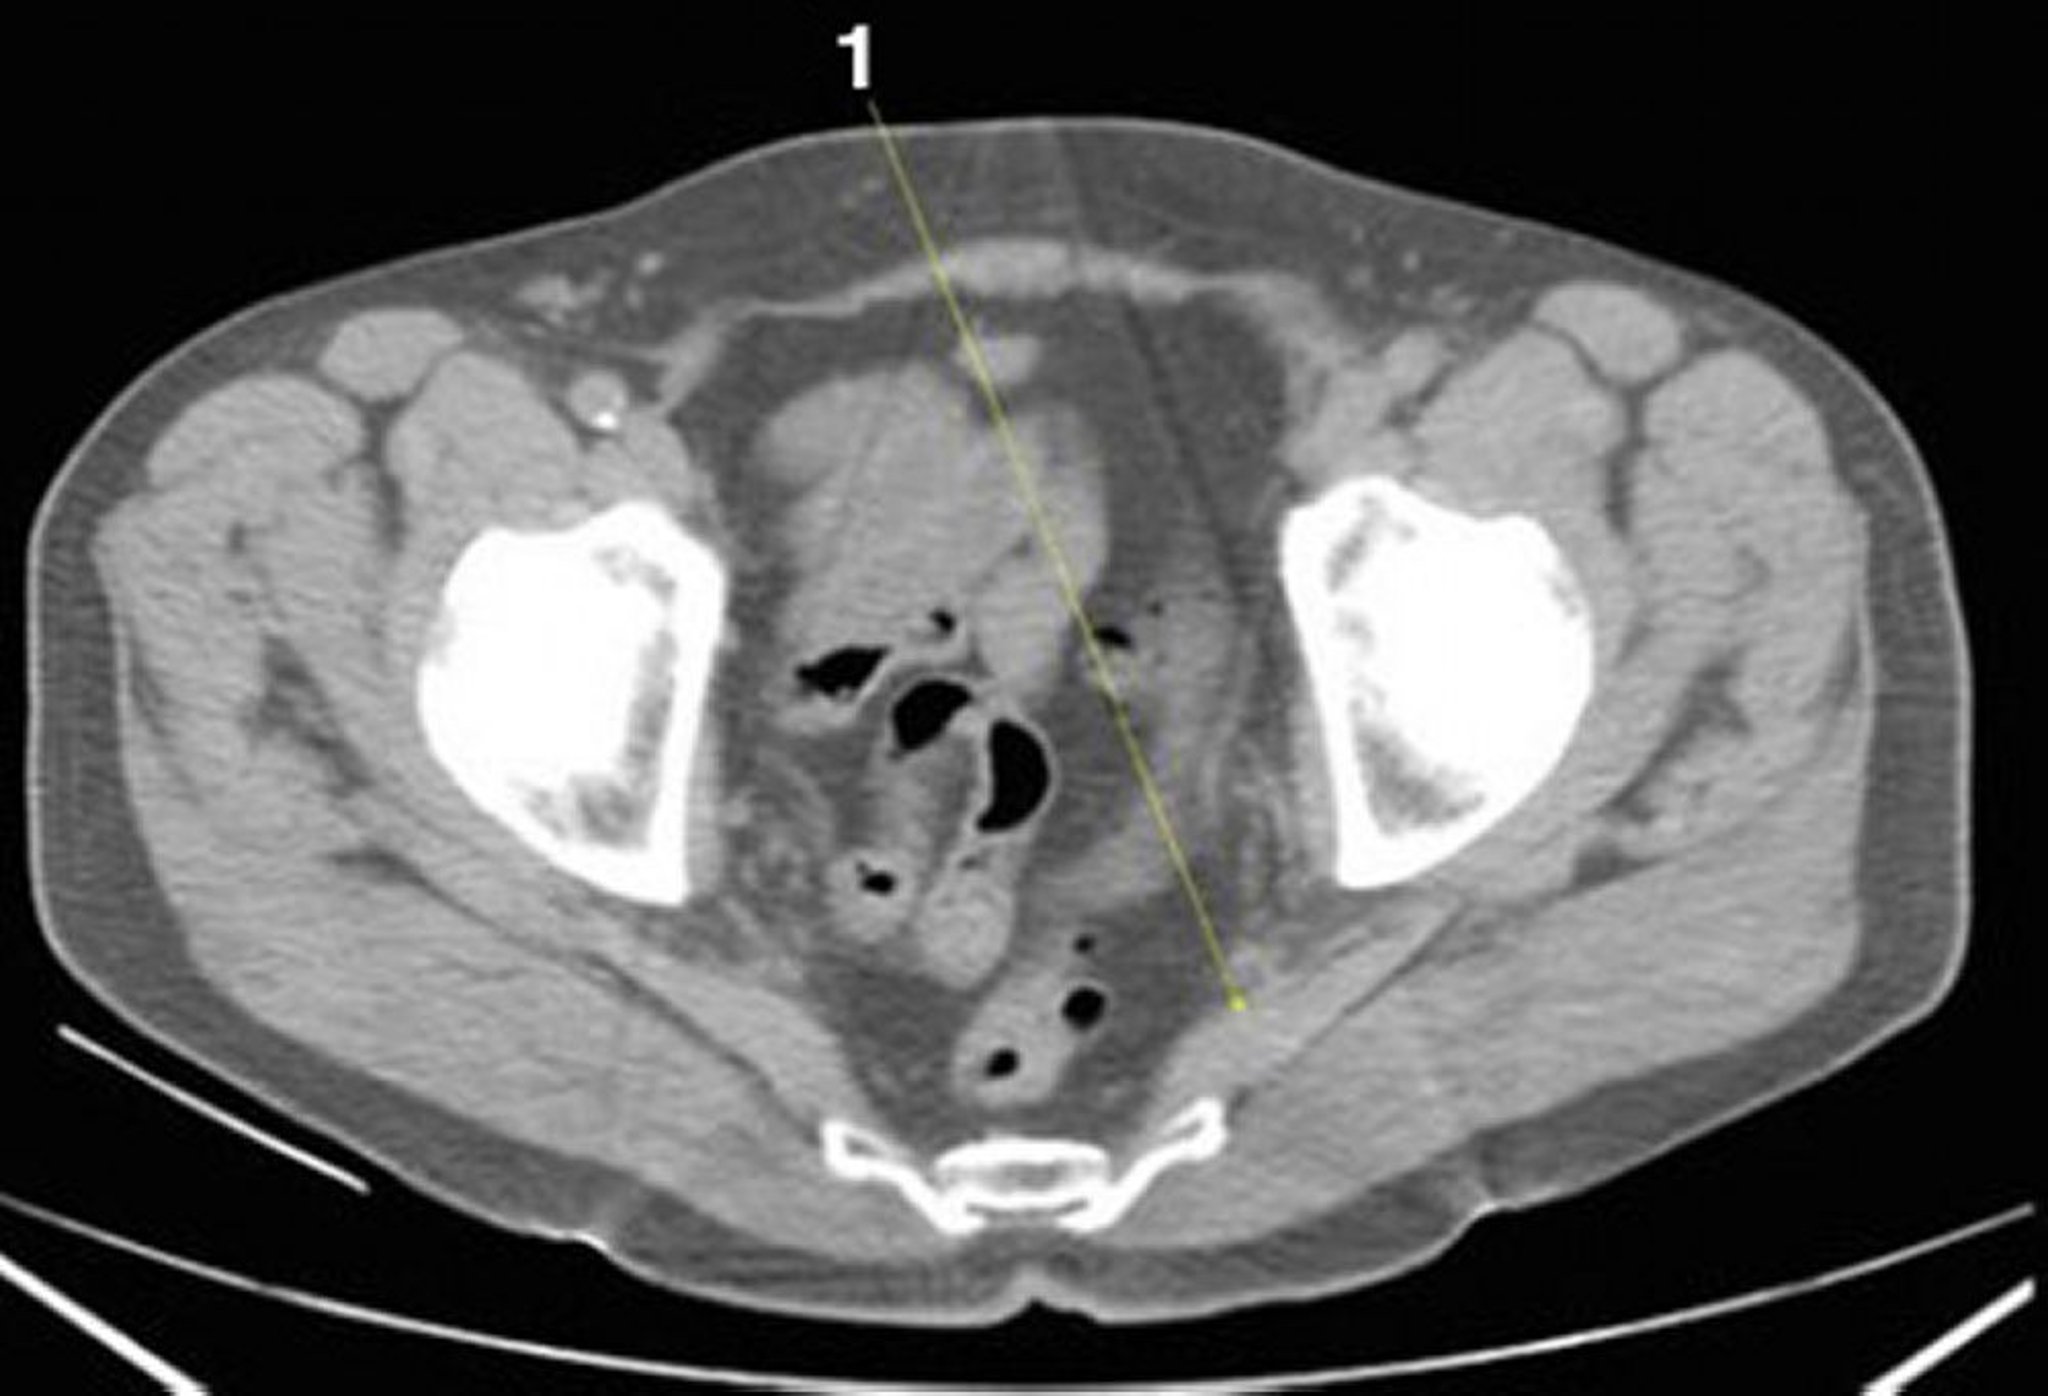

正常解剖を示した腹部および骨盤の単純CT画像(スライド26)

1 = 梨状筋。